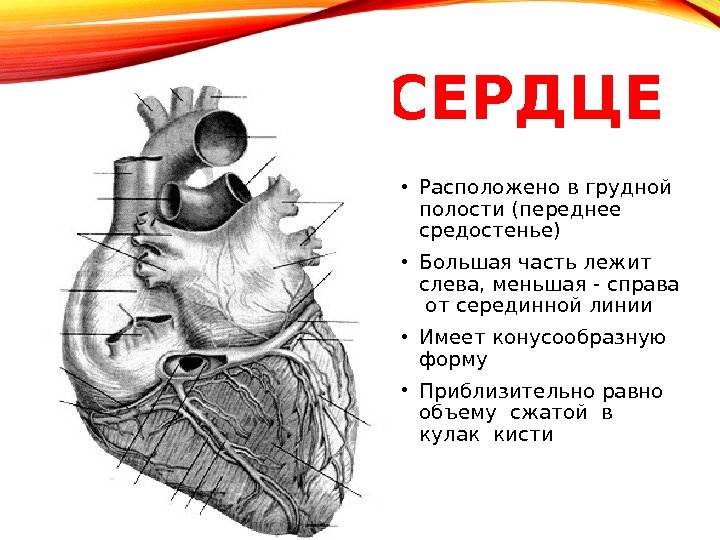

Анатомия Сердца: Расположение и Функции